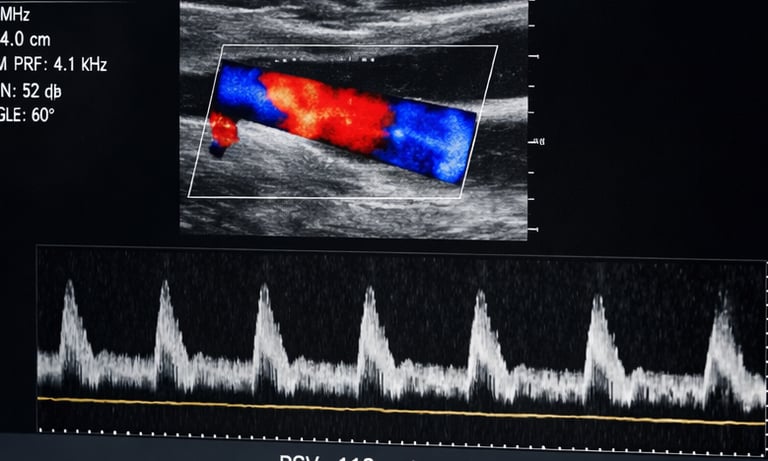

La ecografía de troncos supraaórticos (TSA) permite explorar las arterias carótidas y vertebrales, que son las principales vías de entrada de sangre al cerebro. Es una prueba rápida, indolora y no invasiva, que detecta placas de colesterol, estrechamientos (estenosis) u obstrucciones que pueden provocar un ictus o accidente cerebrovascular. Se trata también de una prueba esencial para el diagnostico de las causas tras un ictus isquémico.

El diagnostico de una estenosis carotídea lo suficientemente relevante mediante eco-doppler TSA, suele ser suficiente para poder indicar un su tratamiento quirúrgico o la colación de un stent que reduzca significativamente el riesgo de sufrir un segundo ictus.

En nuestra consulta de neurología en Burriana (Castellón), este estudio se realiza siempre con equipos de alta resolución y en manos de un neurólogo experto en patología vascular cerebral y acreditado para la realización de estudios con ecografía Doppler. Además, realizamos una evaluación neurológica completa en la que se incluye la instauración de medidas de prevención tras un ictus y la indicación del tratamiento quirúrgico o el stent de la estenosis carotídea.